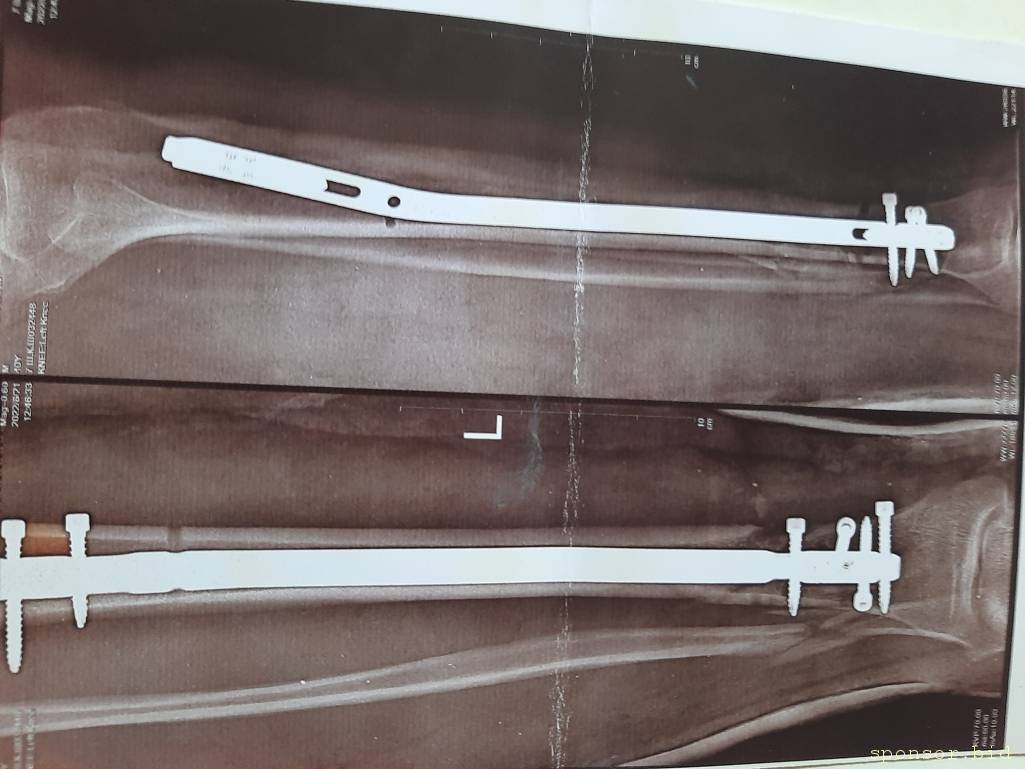

Вот что со мной произошло: летом прошлого 2022 года я неудачно упал, и сломал левую ногу, да так, что всё не закончлось просто гипсом. Перелом был сложным, пришлось делать операцию, ставить биос. Операция прошла с осложнениями, был свищ, нога после операции долго не заживала. Потом сломался крепёжный саморез, стало ещё хуже. Заболела правая нога в колене и бёдре. На приёме у врача сказали нужна операция! И в ближайшее время! Но я на больничном уже целый год, и после такого продолжительного лечения, все мои финансы на нуле. Ходить не могу, спать не могу, мучают постоянные боли. У меня развился сахарный диабет, ноги болят, появилась венозная недостаточность и варикоз. Мне всего 41 год. Получается я останусь инвалидом навсегда... Но у меня есть двое детей 5 и 14 лет... В данный момент я не могу встать на ноги из-за отсутствия финансовых средств. Моя мама Лариса Андреевна, помогает мне по мере своих сил. Ей приходится работать на производстве. Но ей уже 75 лет...

Нужна помощь сыну сотрудницы Не может ходить. - 20230719_135435.jpg

Нужна помощь сыну сотрудницы Не может ходить. - 20230719_135445.jpg